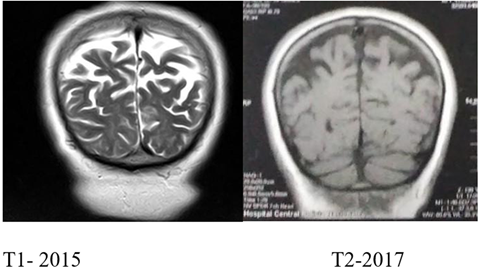

Se encuentra una RM cerebral simple, tomada el 14 de junio de 2015 (ver Figura 1), que registra ligera prominencia de surcos corticales, cisternas basales y sistema ventricular indicativo de atrofia cerebral.

Figura 1 A) IMR de IA corte sagital T1 mayo de 2017. B). C) Corte axial de IA en T1 lóbulos temporales, 2017.

En 2017 se realiza una nueva resonancia, evidenciando “un aumento en la amplitud del sistema ventricular, de los surcos del espacio subaracnoideo periférico y de las cisternas de la base, concluyendo que IA presenta atrofia cerebral difusa con predominio parietal”, figuras 1 y 2.